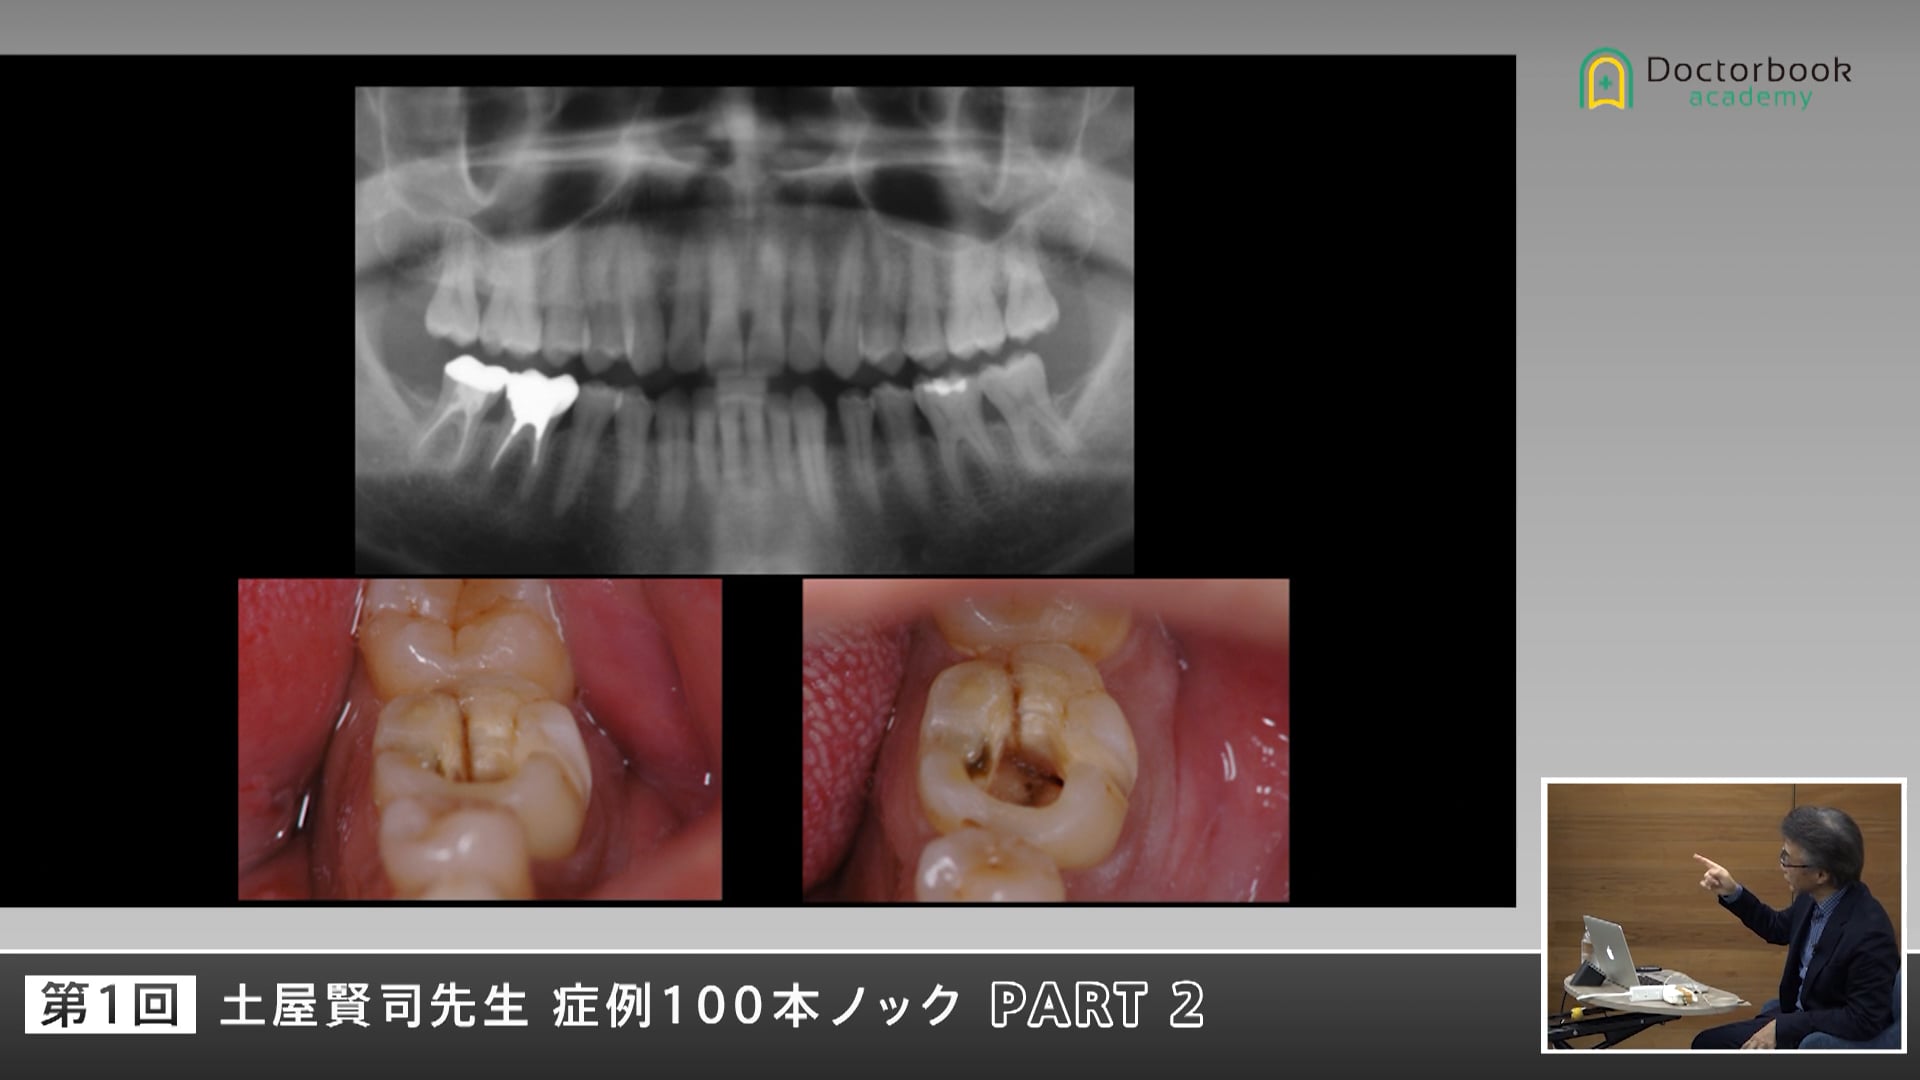

今回の症例では噛んだ時に歯が痛いと来院された患者さんについてです。

まず、どこを診て何をすべきなのでしょうか。

疼痛の原因はなんでしょうか。

レントゲン写真では、どこに着目し、原因を探るべきでしょうか。